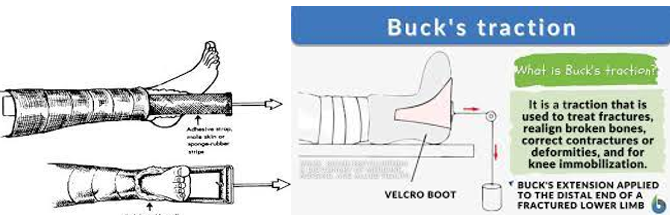

Traction

Uses:

Reduce and/or immobilize a fracture

Align an injured extremity

Allow the extremity to be restored to its normal length

May also reduce pain by decreasing the incidence of muscle spasms.

Extension by a pulling force may be used.

The type of traction used depends on the child’s age, the condition of the soft tissue, and the type and degree of displacement of the fracture:

Manual Traction:

Applied to the body part by hand, placed distally to the fracture site.

Skin Traction:

Pulling mechanisms are attached to the skin with adhesive material or elastic bandage.

Skin must be intact!

Skin Traction

Buck’s Traction:

Reduces femur fractures.

Also used for contractures of the hip or knee.

Force is delivered through a traction boot or skin traction in a straight line.

**Skin must be intact!